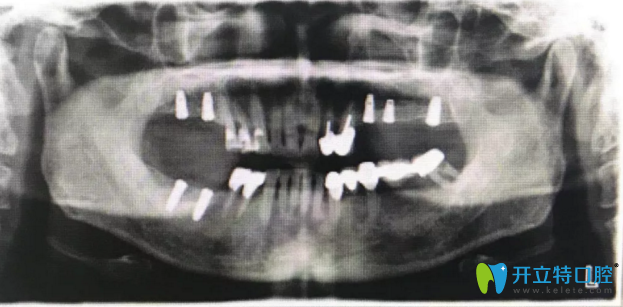

修復完成后拍片

種植修復作為牙缺失修復的選擇,患者戴牙后和活動修復有明顯的區(qū)別,舒適度和咀嚼效果媲美真牙,所以患者反響很好,并決定把左下烤瓷橋拿掉后也種植修復。